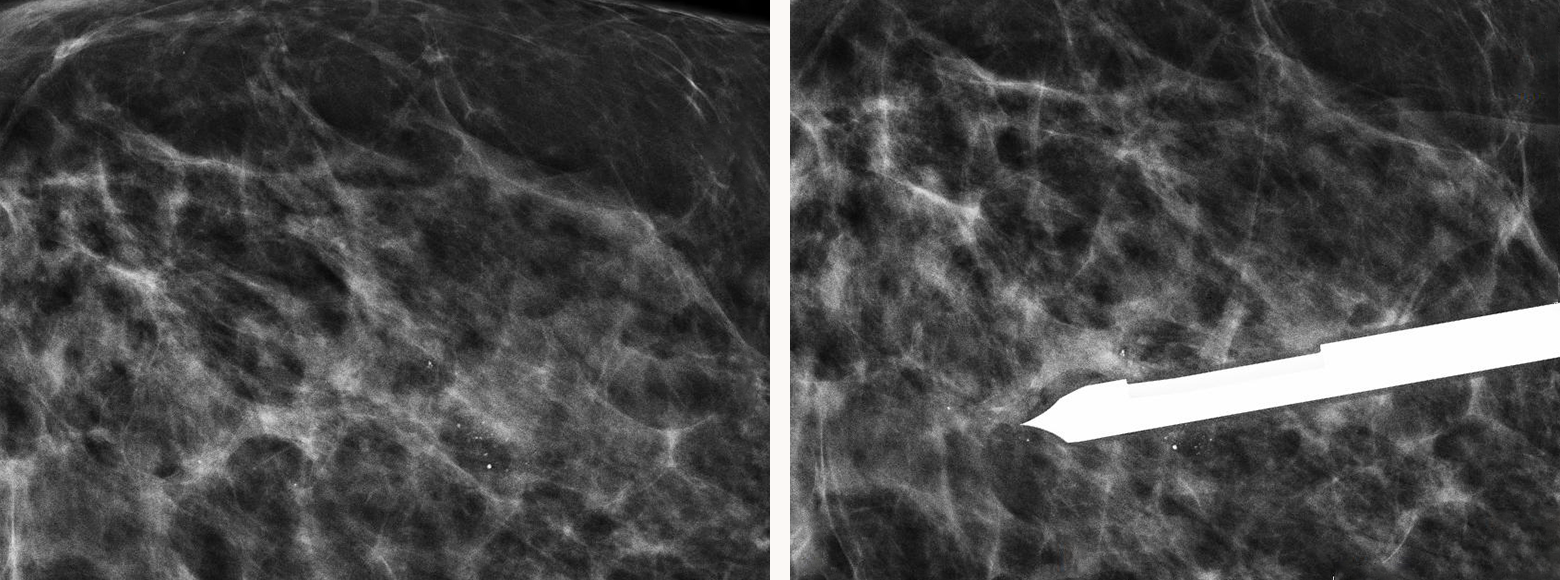

미세석회화 입체정위술이

가능합니다.

미세석회화 입체정위술은 고가의 장비만 있다고

다 시행할 수 있는 것이 아닙니다.

애플유에는 프리미엄 장비는 물론 고도의 기술력과

풍부한 임상 경험을 갖춘 믿을 수 있는 의료진이 있습니다.

미세석회화 입체정위술

- 미세석회화 입체정위술

- 0기 암을 진단하는 고도 정밀 조직검사